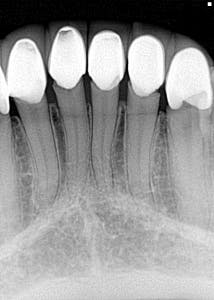

It’s one thing to see an overhang or open margin on one crown or filling, but when you see an entire mouthful of yuck, what do you tell the patient? I’m not a fan of throwing my colleagues in dentistry under the bus, but when I see questionable dental work, I believe the patient needs to know that there are concerns that affect two things: 1. the integrity of the tooth/teeth, and 2. the financial impact it could have.

So, when this patient presented to my office saying that all of her crown work was very recently done, I did a double take and asked, “Really?” Oy vey. Not fun. I recently posted this case in DE’s Breakthrough Clinical Facebook group. The responses are all enlightening and worth your read. With that being said, what would you say to this patient?